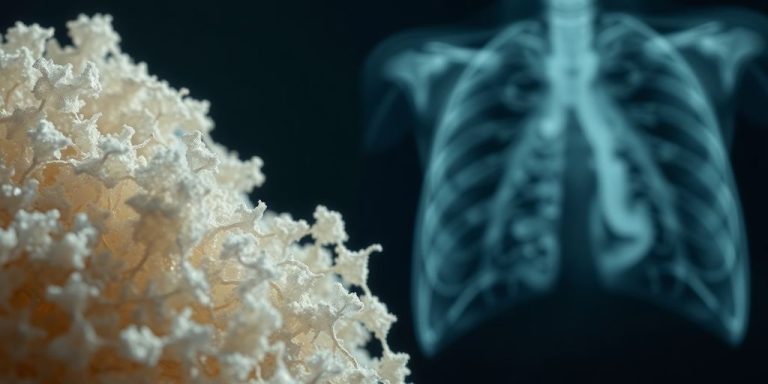

How Asbestos Causes Lung Cancer

So, how does asbestos actually cause lung cancer? Well, it’s all about those tiny fibers. When asbestos-containing materials are disturbed, these microscopic fibers become airborne. When inhaled, these fibers can become lodged in the lungs. Over time, the body’s natural defenses can’t break down these fibers, leading to chronic inflammation and scarring. This can lead to:

The prolonged irritation and damage to lung cells can eventually cause them to become cancerous. It’s a slow process, often taking decades after the initial exposure for lung cancer to develop.

Imaging Tests

First up are the imaging tests. Think of these as taking pictures of your lungs. X-rays are usually the first thing doctors do. They’re quick and easy, but they don’t always show everything. Then there are CT scans, which are more detailed. They can spot smaller abnormalities that X-rays might miss. MRIs are sometimes used too, especially if the doctor needs a closer look at certain areas. PET scans can help see if the cancer has spread to other parts of the body. These scans use a radioactive tracer to highlight cancerous cells. It’s kind of like a high-tech game of hide-and-seek, but with cancer cells.